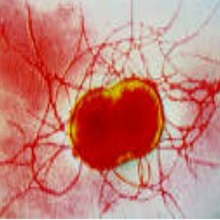

| Гастритис је хистолошки доказана инфламација слузокоже желуца. Дели се на акутни и хронични гастритис. Етиолошка подела гастритисе дели на инфективне и неинфективне. Откриће Хеликобактер пилори инфекције потпуно је променило поглед на етиологију гастритиса. Данас се зна да је најчешћи узрочник (у преко 90% случајева) инфективног гастритиса Хеликобактер пилори, а потом Хеликобактер хеилмани и ентеровируси. |